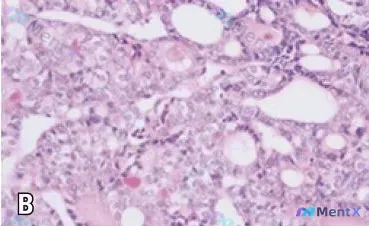

最近看到一例切除肾上腺肿瘤的H&E染色切片,整理了一下读片思路和大家分享。 基本信息 - 标本来源:切除的肾上腺肿瘤 - 染色方法:Hematoxylin and eosin (H&E) - 视野:高倍镜,标尺 300μm 镜下关键特征 1. 组织架构:可见明显的管状/腺管状排列模式,部分管腔不规则...